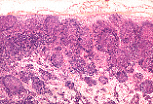

输入淋巴管汇入淋巴结的结缔组织被膜中。这些淋巴管衬有内皮细胞,且可出现瓣膜结构。

它们开口于被膜下窦(该窦位于被膜与皮质淋巴小结之间)。

该窦的壁衬有 内皮样细胞(衬细胞) ,与输入淋巴管的内皮细胞相延续。